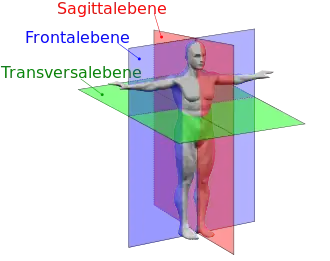

Die in der nebenstehenden Abbildung grün dargestellte Ebene ist eine Transversalebene. Alle zu ihr parallelen, nach oben oder unten verschobenen Ebenen sind ebenfalls Transversalebenen. Es gibt unendlich viele parallel zueinander liegende Transversalebenen. Drehungen um die Längsachse sind Bewegungen in diesen Ebenen.